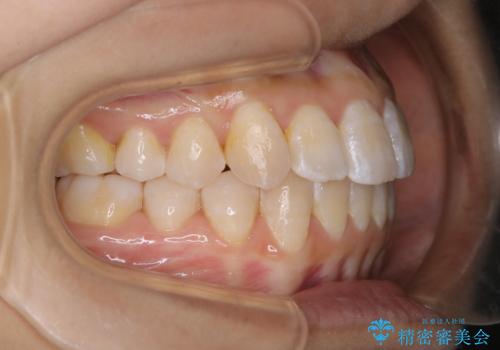

前歯のがたつきとオープンバイト:インビザラインでまとめて治す

- 噛み合わせと、前歯のがたつきが気になるとご相談にいらした方です。インビザラインFULLで綺麗な歯並びと噛み合わせを作ることが出来ました。

オープンバイトの方への治療は、通常抜歯を行いワイヤーによる矯正治療を行うことが多いですが、今回はインビザラインの特性を生かし、非抜歯にて綺麗な歯並びを作ることが出来ました。

舌癖がある方は、歯を内側から押し出す力が日常的に働くため、矯正治療後も歯と歯の隙間が開いてしまうなどの後戻りのリスクが高いことが知られています。舌の正しいポジショニングやお口周りの筋肉のトレーニングを行うことで後戻りのリスクを減らすことが可能です。